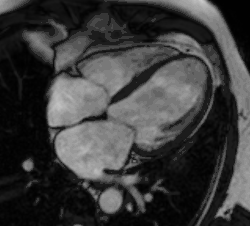

Cardiac magnetic resonance imaging (cardiac MRI, CMR), also known as cardiovascular MRI, is a magnetic resonance imaging (MRI) technology used for non-invasive assessment of the function and structure of the cardiovascular system.[2] Conditions in which it is performed include congenital heart disease, cardiomyopathies and valvular heart disease, diseases of the aorta such as dissection, aneurysm and coarctation, coronary heart disease. It can also be used to look at pulmonary veins.[3]

A CMR study typically comprises a set of sequences in a protocol tailored to the specific indication for the exam.[21] A study begins with localisers to assist with image planning, and then a set of retrospectively-gated cine sequences to assess biventricular function in standard orientations. Contrast medium is given intravenously to assess myocardial perfusion and LGE. Phase contrast imaging may be used to quantify valvular regurgitant fraction and shunt volume. Additional sequences may include T1 and T2-weighted imaging and MR angiography. Examples are below:

Heart function using cine imaging

Functional and structural information is acquired using bSSFP cine sequences. These are usually retrospectively-gated and have intrinsically high contrast in cardiac imaging due to the relatively high T2:T1 ratio of blood compared to myocardium. Images are typically planned sequentially to achieve the standard cardiac planes used for assessment. Turbulent flow causes dephasing and signal loss allowing valvular disease to be qualitatively appreciated. The left ventricular short axis cines are acquired from base to apex and are used for quantifying end-diastolic and end-systolic volumes, as well as myocardial mass. Tagging sequences excite a grid pattern that deforms with cardiac contraction allowing strain to be assessed.